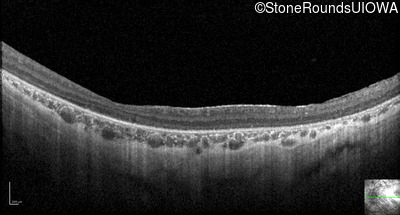

Optical Coherence Tomography - Right - 10/300 sc

Exemplar / OCT Stack